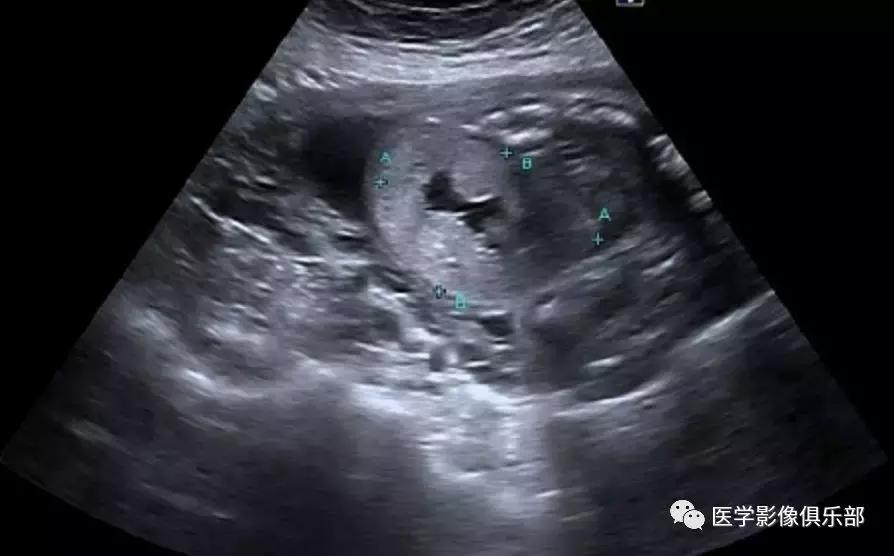

[典型病例二]:45岁,女性患者,腹部不适。家族史是动脉瘤性蛛网膜下腔出血和肾损害。

CTMPR冠状位重建显示双侧肾脏体积明显增大,肾脏皮质及髓质分界不清,弥漫大小不等的囊肿,边界光滑锐利,肝脏实质内亦可见多发大小不等的囊肿。